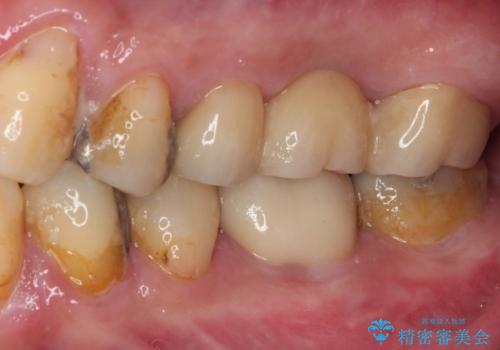

前後の歯は銀歯が装着されていたため、ブリッジによる補綴治療として、前後の歯もセラミックに置き換えることとしました。

下顎の根管治療がされた大臼歯は咬合時に痛みが認められたため、再度根管治療を行った後に補綴治療することとしました。